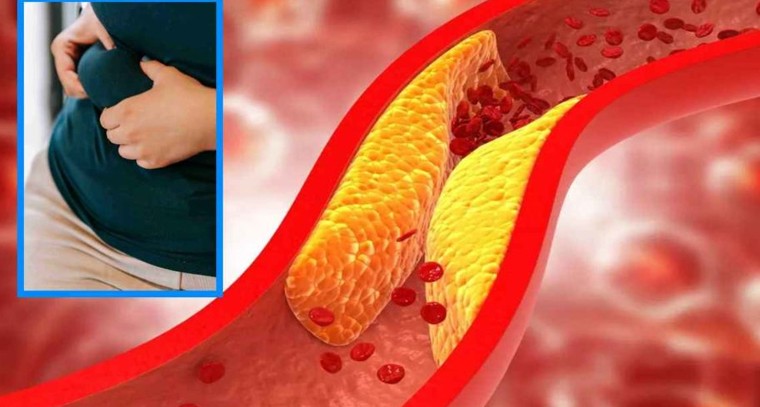

మటన్ ఎలా పడితే అలా తినకండి.. కొలెస్ట్రాల్ పెరగడంతో పాటు క్యాన్సర్ వచ్చే ప్రమాదం

అధిక కొలెస్ట్రాల్కి ఎలా చెక్ పెట్టాలి..